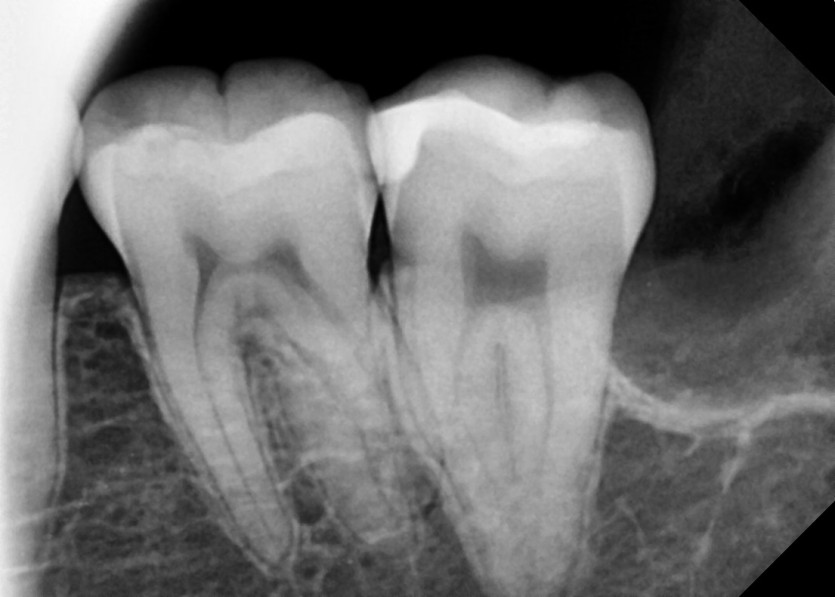

#28,38 사랑니 발치

구강 외과 전문의가 당일 발치했습니다.